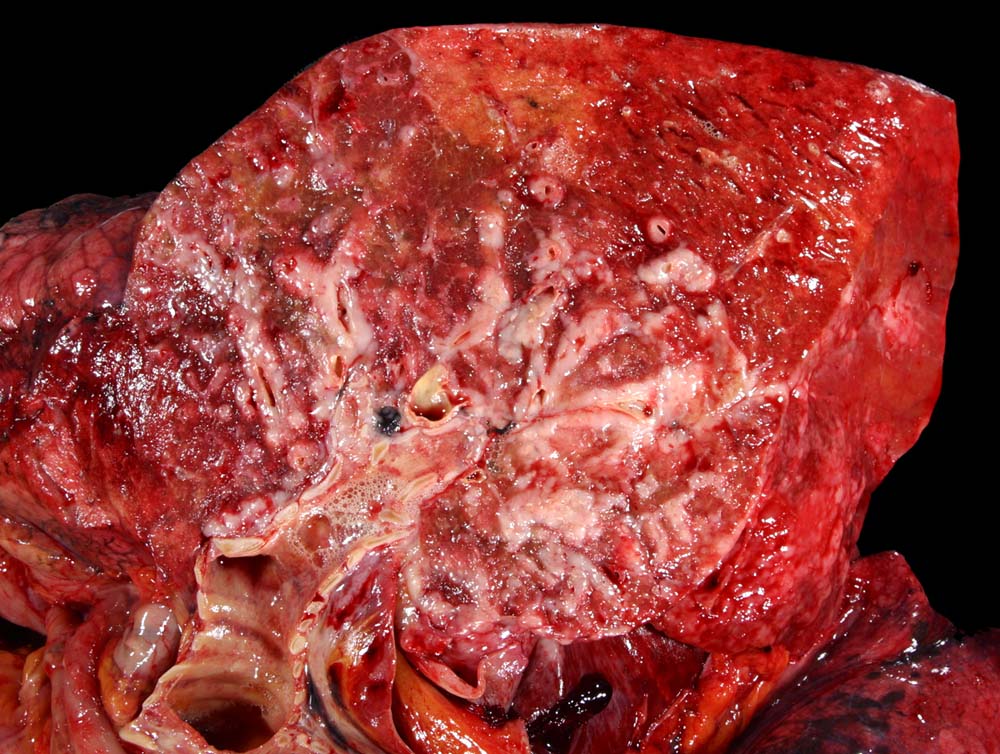

Das metastatische Wachstumsmuster von primären Bronchuskarzinomen und extrapulmonalen Tumoren innerhalb der Lunge ist variabel. Hämatogene Metastasen imponieren makroskopisch als multiple scharf begrenzte rundliche Knoten in allen Lappen meist in peripherer Lage. Der metastatische Befall von Lymphknoten kann durch direkte Tumorinfiltration durch den Primärtumor erfolgen (=per continuitatem) oder über die Lymphgefässe. Bei einer ausgeprägten lymphogenen Tumorausbreitung erscheinen subpleurale mit Tumor gefüllte Lymphgefässe makroskopisch als prominente weisse Streifen. Mikroskopisch lassen sich Tumorinfiltrate in peribronchialen und perivaskulären Lymphgefässen nachweisen (=Lymphangiosis carcinomatosa). Hepatozelluläre Karzinome metastasieren typischerweise in Form von Tumorembolien (> 1279) hämatogen in die Lunge.

Makroskopie

Befund

Pathologischer Befund

Normalbefund